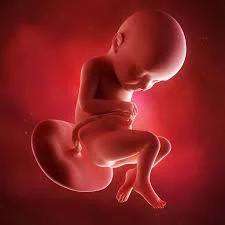

• Semana 40

Semana 40

El feto mide alrededor de 50 cm y pesa entre 3 y 4 kg. Está completamente desarrollado y en posición para nacer. Los huesos del cráneo son flexibles para facilitar el parto. El feto está preparado para respirar por sí mismo, y su corazón y pulmones están listos para funcionar. El nacimiento puede ocurrir en cualquier momento.